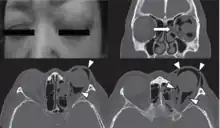

| Woman with preorbital swelling in orbital emphysema shown in CT scans | |

The signs and symptoms of orbital emphysema vary depending on the original cause, but it is preliminary associated with swelling, bruising, and tenderness around the impacted eye.[29] It may also involve proptosis or the deterioration of vision, typically diplopia.[1][23] The entrapped air may cause an acute increase in the intraocular pressure or vascular compromise that restrict ocular motility, prohibit the closure of eyelids, and the loss of sensation over the upper cheek areas.[30]